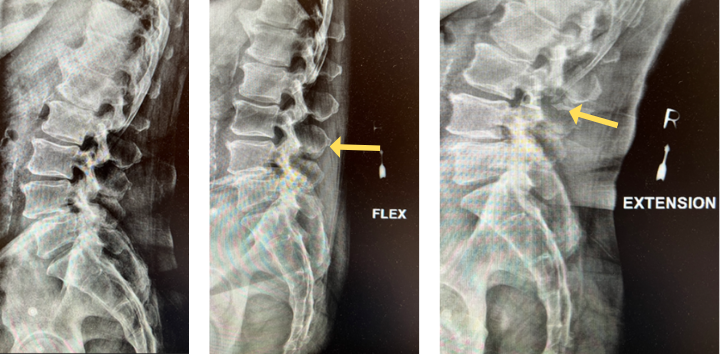

The grade 1 spondylolisthesis at L4/L5 requires both decompression at the L4/L5 level but also fusion because of the instability with motions. Here are three standing x-rays: one in the neutral position, one in flexion, and one in extensions. Notice the movement in the vertebral bodies at L4 and L5. This is abnormal motion and it can contribute to back pain and increase stenosis in certain positions. Thus, it requires decompression and stabilization with fusions.

Image 2. This shows the lumbar spine in motion. Notice the L4 and L5 level changes with flexion and extension. Notice the L2 and L3 levels do not have that type of motion. This is instability.